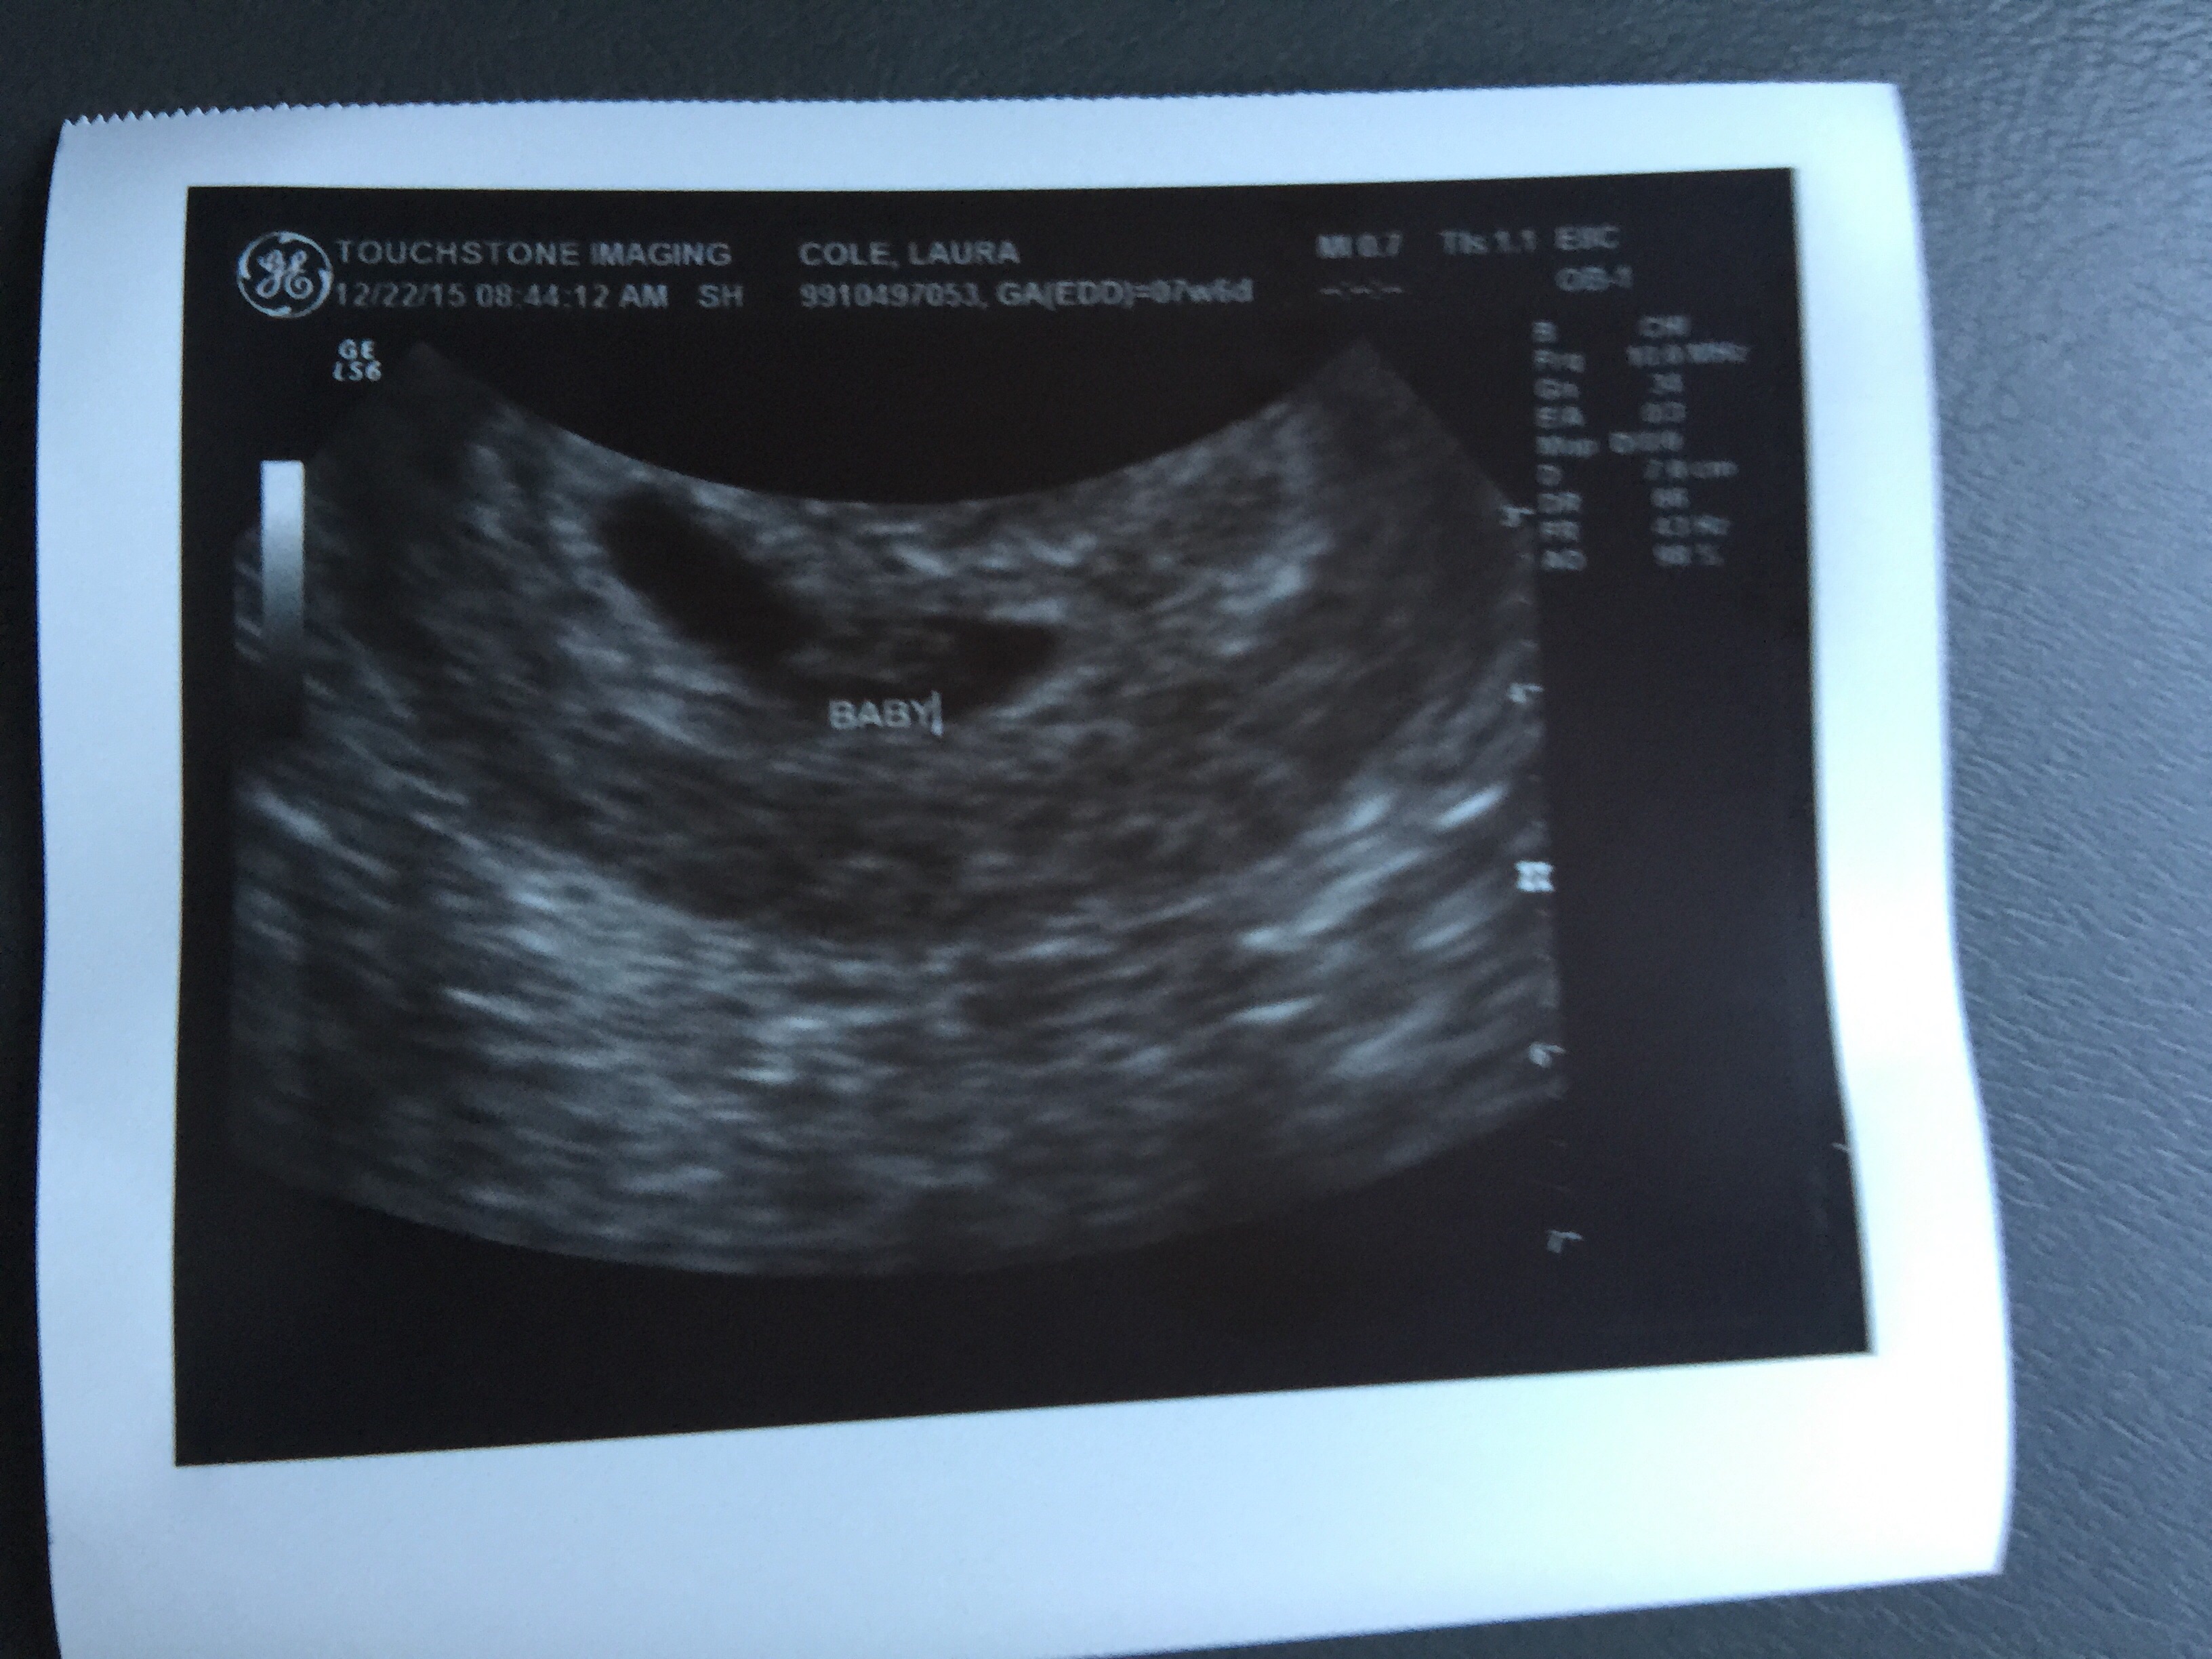

This was our little peanut today at 7 weeks 6 days, transvaginal ultrasound. Any guesses by Ramzi method?